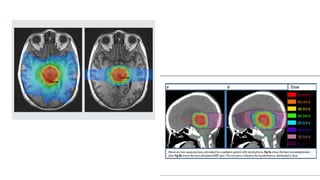

• Computed tomography (CT) -thermoplastic mask before RT planning

• Target and organs at risk (OARs) were delineated on the acquired CT

images by referring to the MRI findings.

• Tumor was partially resected-both gadolinium-enhanced lesions and high-

intensity lesions on the T2-weighted images,

• GTV-TUMOR +ODEMA

• CTV- 0.5–2.0-cm margin from the area excluding bone.

• PTV -0.5-cm margin to CTV.

• OARs-chiasm, spinal cord, bilateral optic nerves, eyeballs and lens,

Steps- • Computed tomography(CT) -thermoplastic mask before RT planning • Target and organs at risk (OARs) were delineated on the acquired CT images by referring to the MRI findings. • Tumor was partially resected-both gadolinium-enhanced lesions and high- intensity lesions on the T2-weighted images, • GTV-TUMOR +ODEMA • CTV- 0.5–2.0-cm margin from the area excluding bone. • PTV -0.5-cm margin to CTV. • OARs-chiasm, spinal cord, bilateral optic nerves, eyeballs and lens,